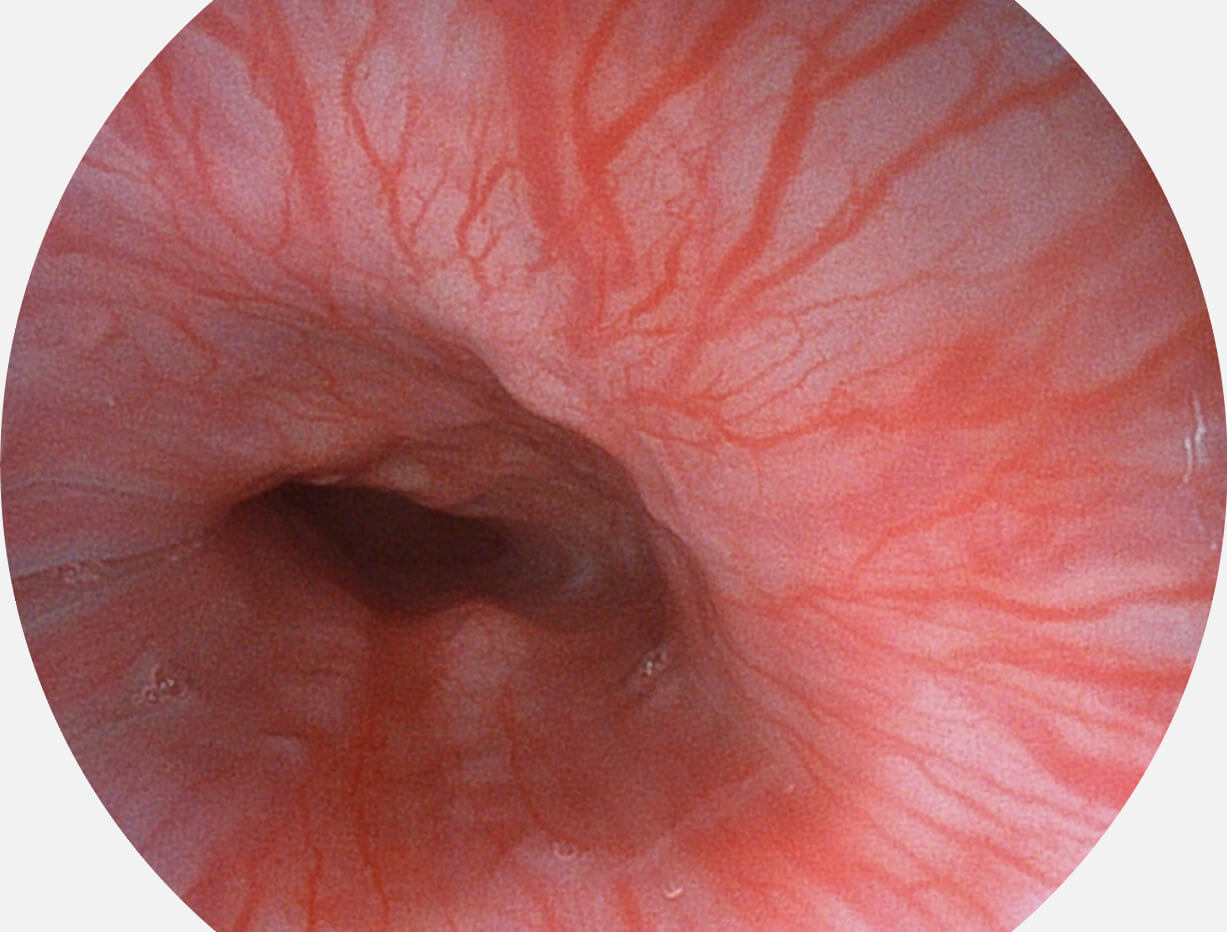

• 1080P全高清画质

采用无损耗高清数字接口,视频输出分辨率≥1920×1080,图像清晰、细腻。

• VLS-55系列四波长LED光源

采用光路合束技术,光谱自由度高,实现了更丰富的照明模式,染色模式SFI及VIST,从远景到近景,助力消化道早期疾病诊断。